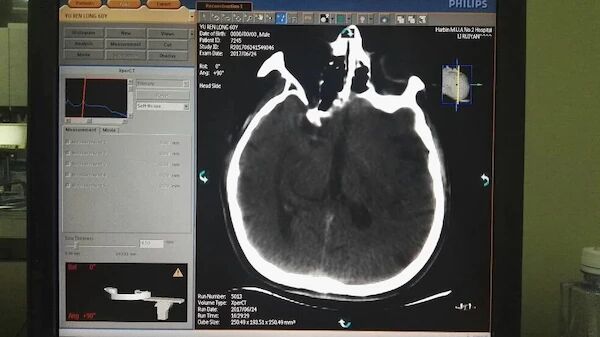

手术前的CT和多模MR

术后即刻CT

术后12小时头CT,病人目前语言功能改善,右半身肌力3级以上

术后48小时头CT